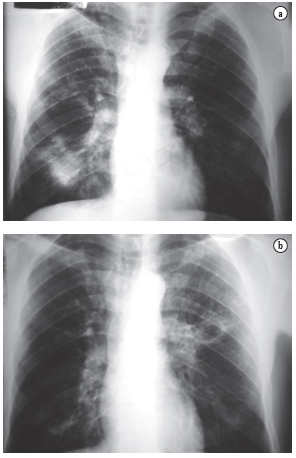

As queixas clínicas, os dados de exame físico e as alterações radiológicas apresentadas por esses doentes, na maioria das vezes, não permitiram a diferenciação segura entre as duas doenças (Figuras 2, 3 e 4).

Destes 227, 36 pacientes (15,8%) relatavam tratamento prévio para TB. No entanto, apenas 18 (7,9%) apresentavam baciloscopia de escarro positiva para bacilos álcool-ácido resistentes ou cultura de escarro positiva para Mycobacterium tuberculosis. Destes, 17 eram do sexo masculino, todos da raça branca, apresentando média de idade de 43,3 anos (30 a 56 anos) na ocasião do diagnóstico. Os outros 18 pacientes, todos da raça branca e do sexo masculino, com média de idade de 49 anos (35 a 69 anos) na ocasião do diagnóstico, apresentaram resultados negativos e não melhoraram clinicamente com o tratamento para TB, respondendo, porém, ao tratamento instituído para PCM (Figura 1).